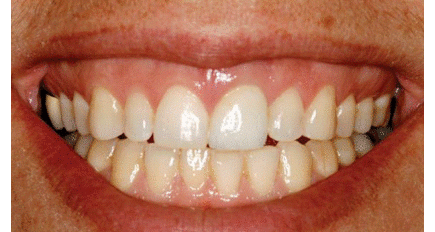

Dans l'exercice à long terme de la dentisterie globale, la forme, fonction, l'esthétique et la stabilité sont des attributs pour ...